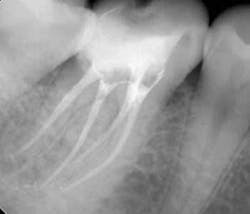

Once all of the canals are found, I will go through the series of Sybron Twisted Files size 25 tapering from 0.10 to 0.80 to 0.60 to 0.40. The 0.40 file should reach the working length for most canals. On a large palatal or distal canal, the 0.60 TF will usually reach working length. After which, using the crown-down technique with the Brasseler EndoSequence rotary files, instrument each canal until files reach the working length. Once instrumentation is complete, take a P.A. with gutta-percha to confirm instrumentation to working length. I find it much easier to take working length films with gutta-percha rather than files (which may fall out, bend, or separate)

Canals are carefully dried with paper points. Insert the gutta-percha with AH sealer in the canal to working length, and take it back out. Add additional sealer to the gutta-percha, and then in a gentle pumping motion insert gutta-percha back to working length. Sear off access with a thermal pen and apply gentle pressure with a condenser.

Using a pumping motion and adding additional sealer ensures that voids within the canals get filled. This generates the “puff” effect with small amount of sealer being extruded from the apex of canals. It also helps ensure accessory canals are not left unfilled.